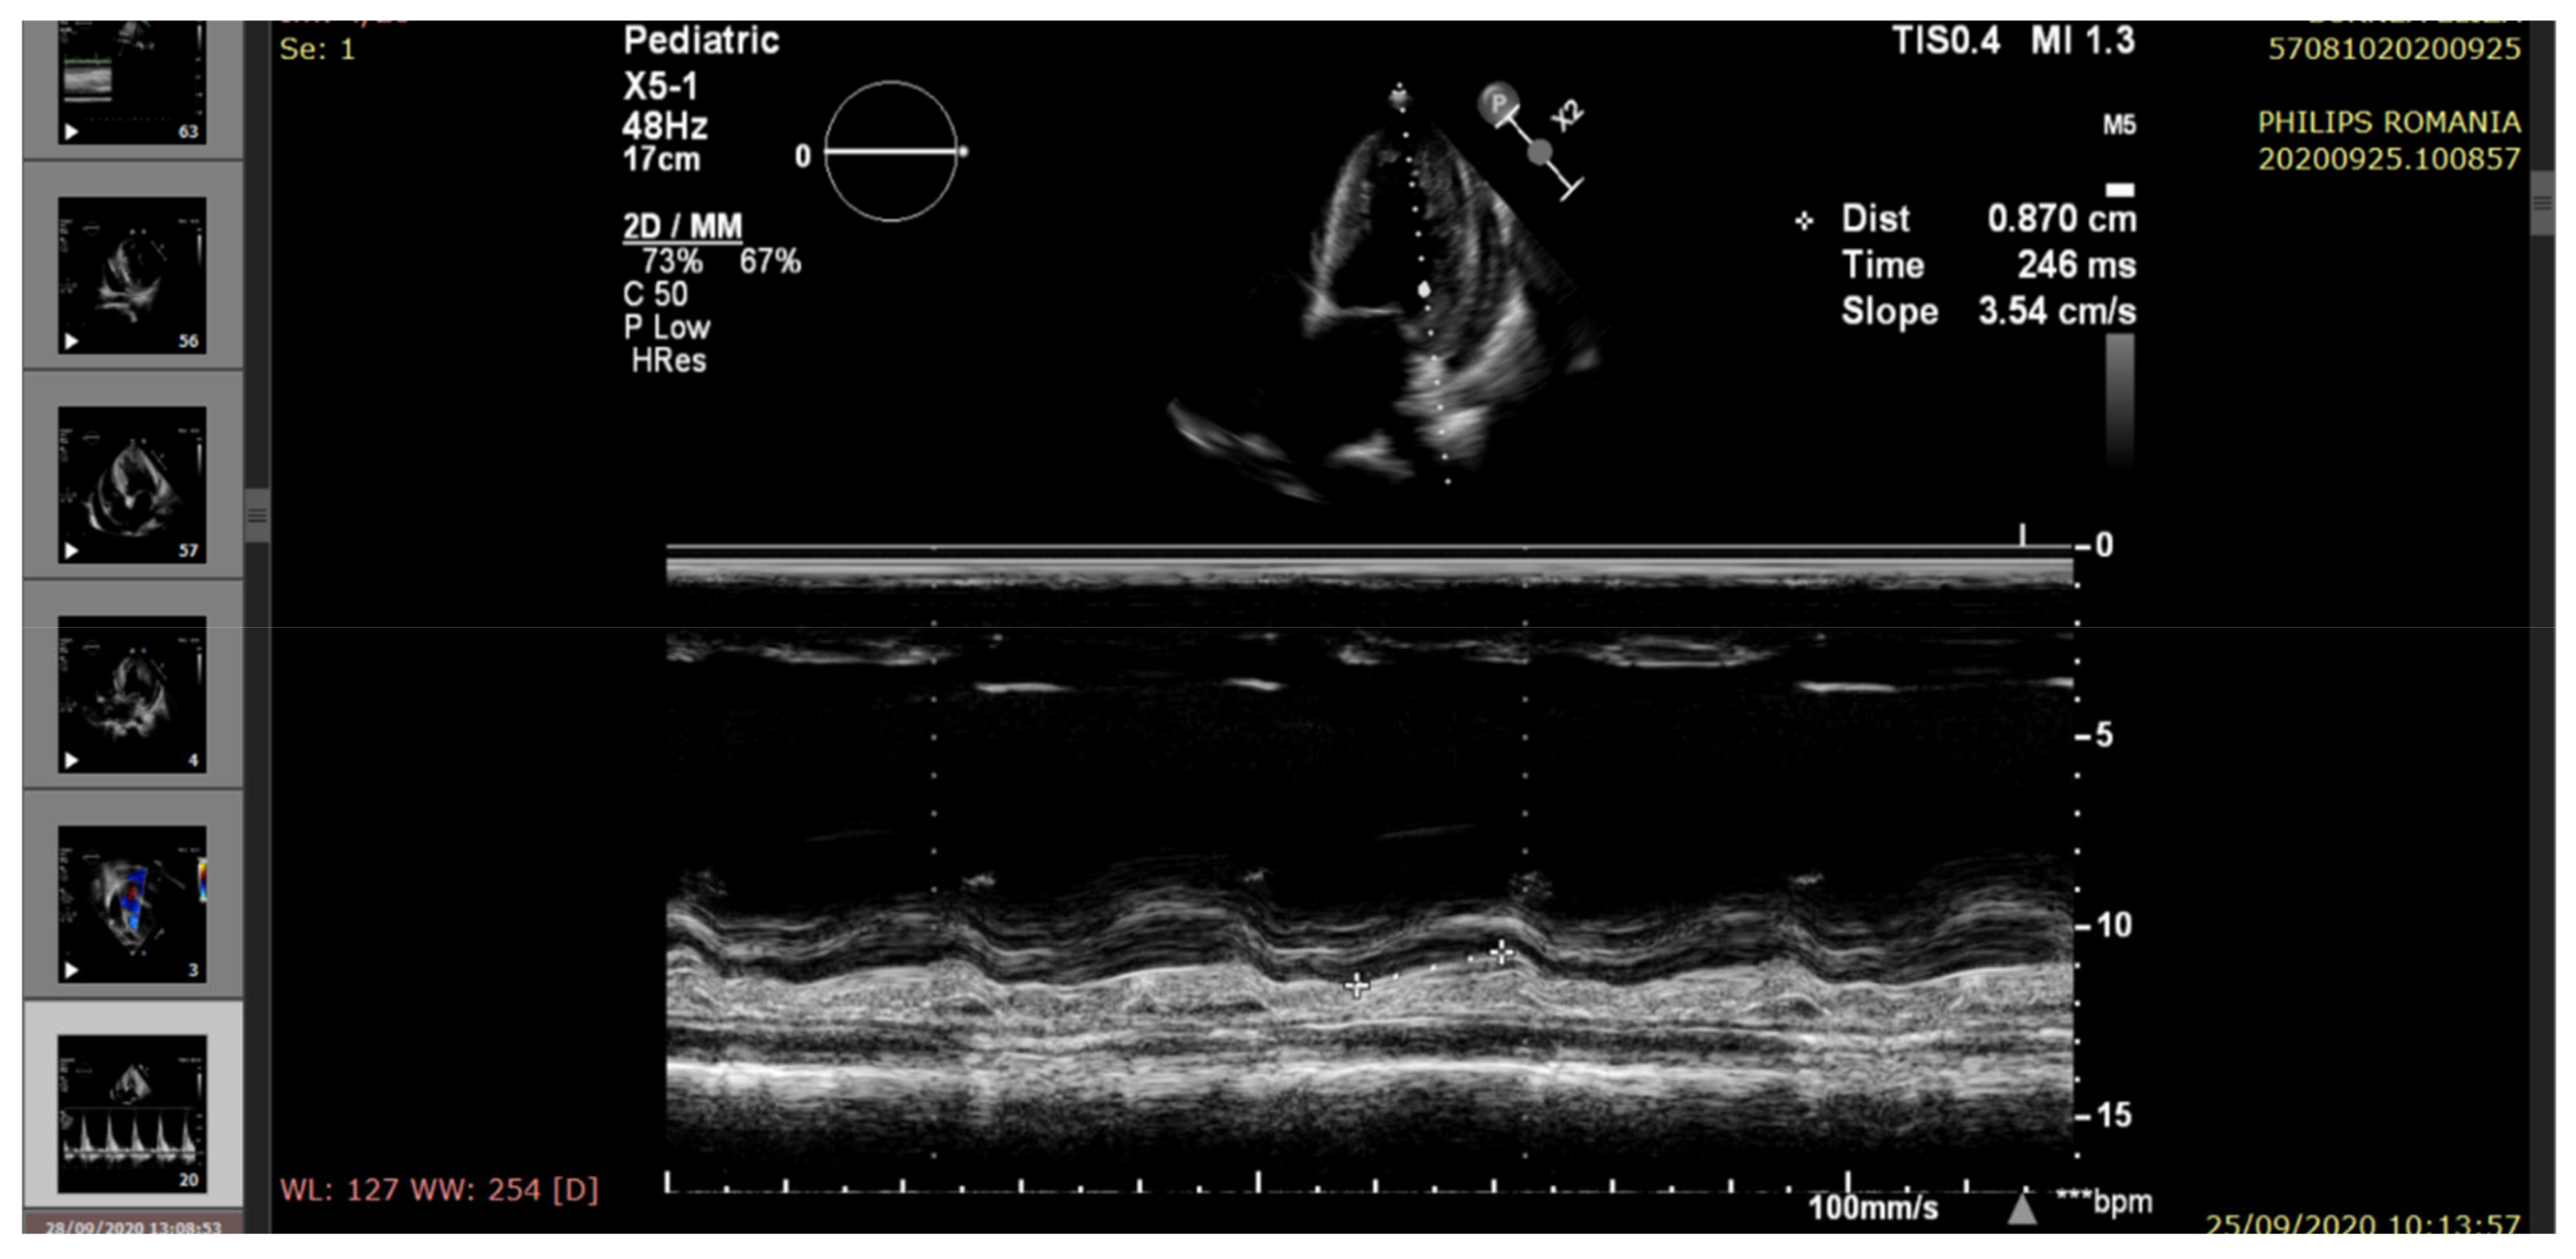

| Mitral annular plane systolic excursion (MAPSE) (mm) (M-mode) | 16.4 ± 2.4 | 15 | 9.2 | 12.2 | 8.3 |

| Mitral diastolic pattern | Normal | Impaired relaxation | Pseudonormal filling | Impaired relaxation | Restrictive filling |